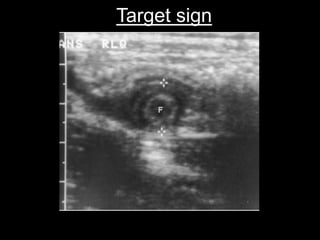

 Target appearance : If fluid is present in the lumen, a

fluid-filled center and surrounded by a echogenic

mucosa and submucosa and hypoechoic muscularis,

may be seen when imaging in the axial plane

Target sign